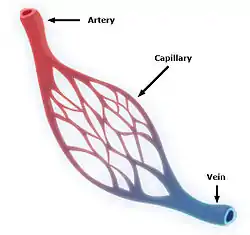

The human circulatory system (simplified). Red indicates oxygenated blood carried in arteries. Blue indicates deoxygenated blood carried in veins. Capillaries join the arteries and veins. | |

The network of blood vessels are the great vessels of the heart including large elastic arteries, and large veins; other arteries, smaller arterioles, capillaries that join with venules (small veins), and other veins. The circulatory system is closed in vertebrates, which means that the blood never leaves the network of blood vessels. Some invertebrates such as arthropods have an open circulatory system. Diploblasts such as sponges, and comb jellies lack a circulatory system.

The blood vessels of the circulatory system are the arteries, veins, and capillaries. The large arteries and veins that take blood to, and away from the heart are known as the great vessels.[14]

Arteries branch into small passages called arterioles and then into the capillaries.[19] The capillaries merge to bring blood into the venous system.[20]

Capillaries merge into venules, which merge into veins.[21] The venous system feeds into the two major veins: the superior vena cava – which mainly drains tissues above the heart – and the inferior vena cava – which mainly drains tissues below the heart. These two large veins empty into the right atrium of the heart.[22]